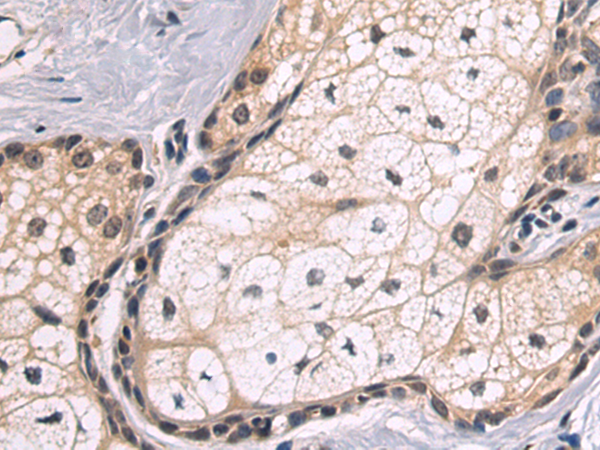

分类: 科研抗体货号: P10604别名: MCS; MOS; HMCS应用: IHC反应种属: Human